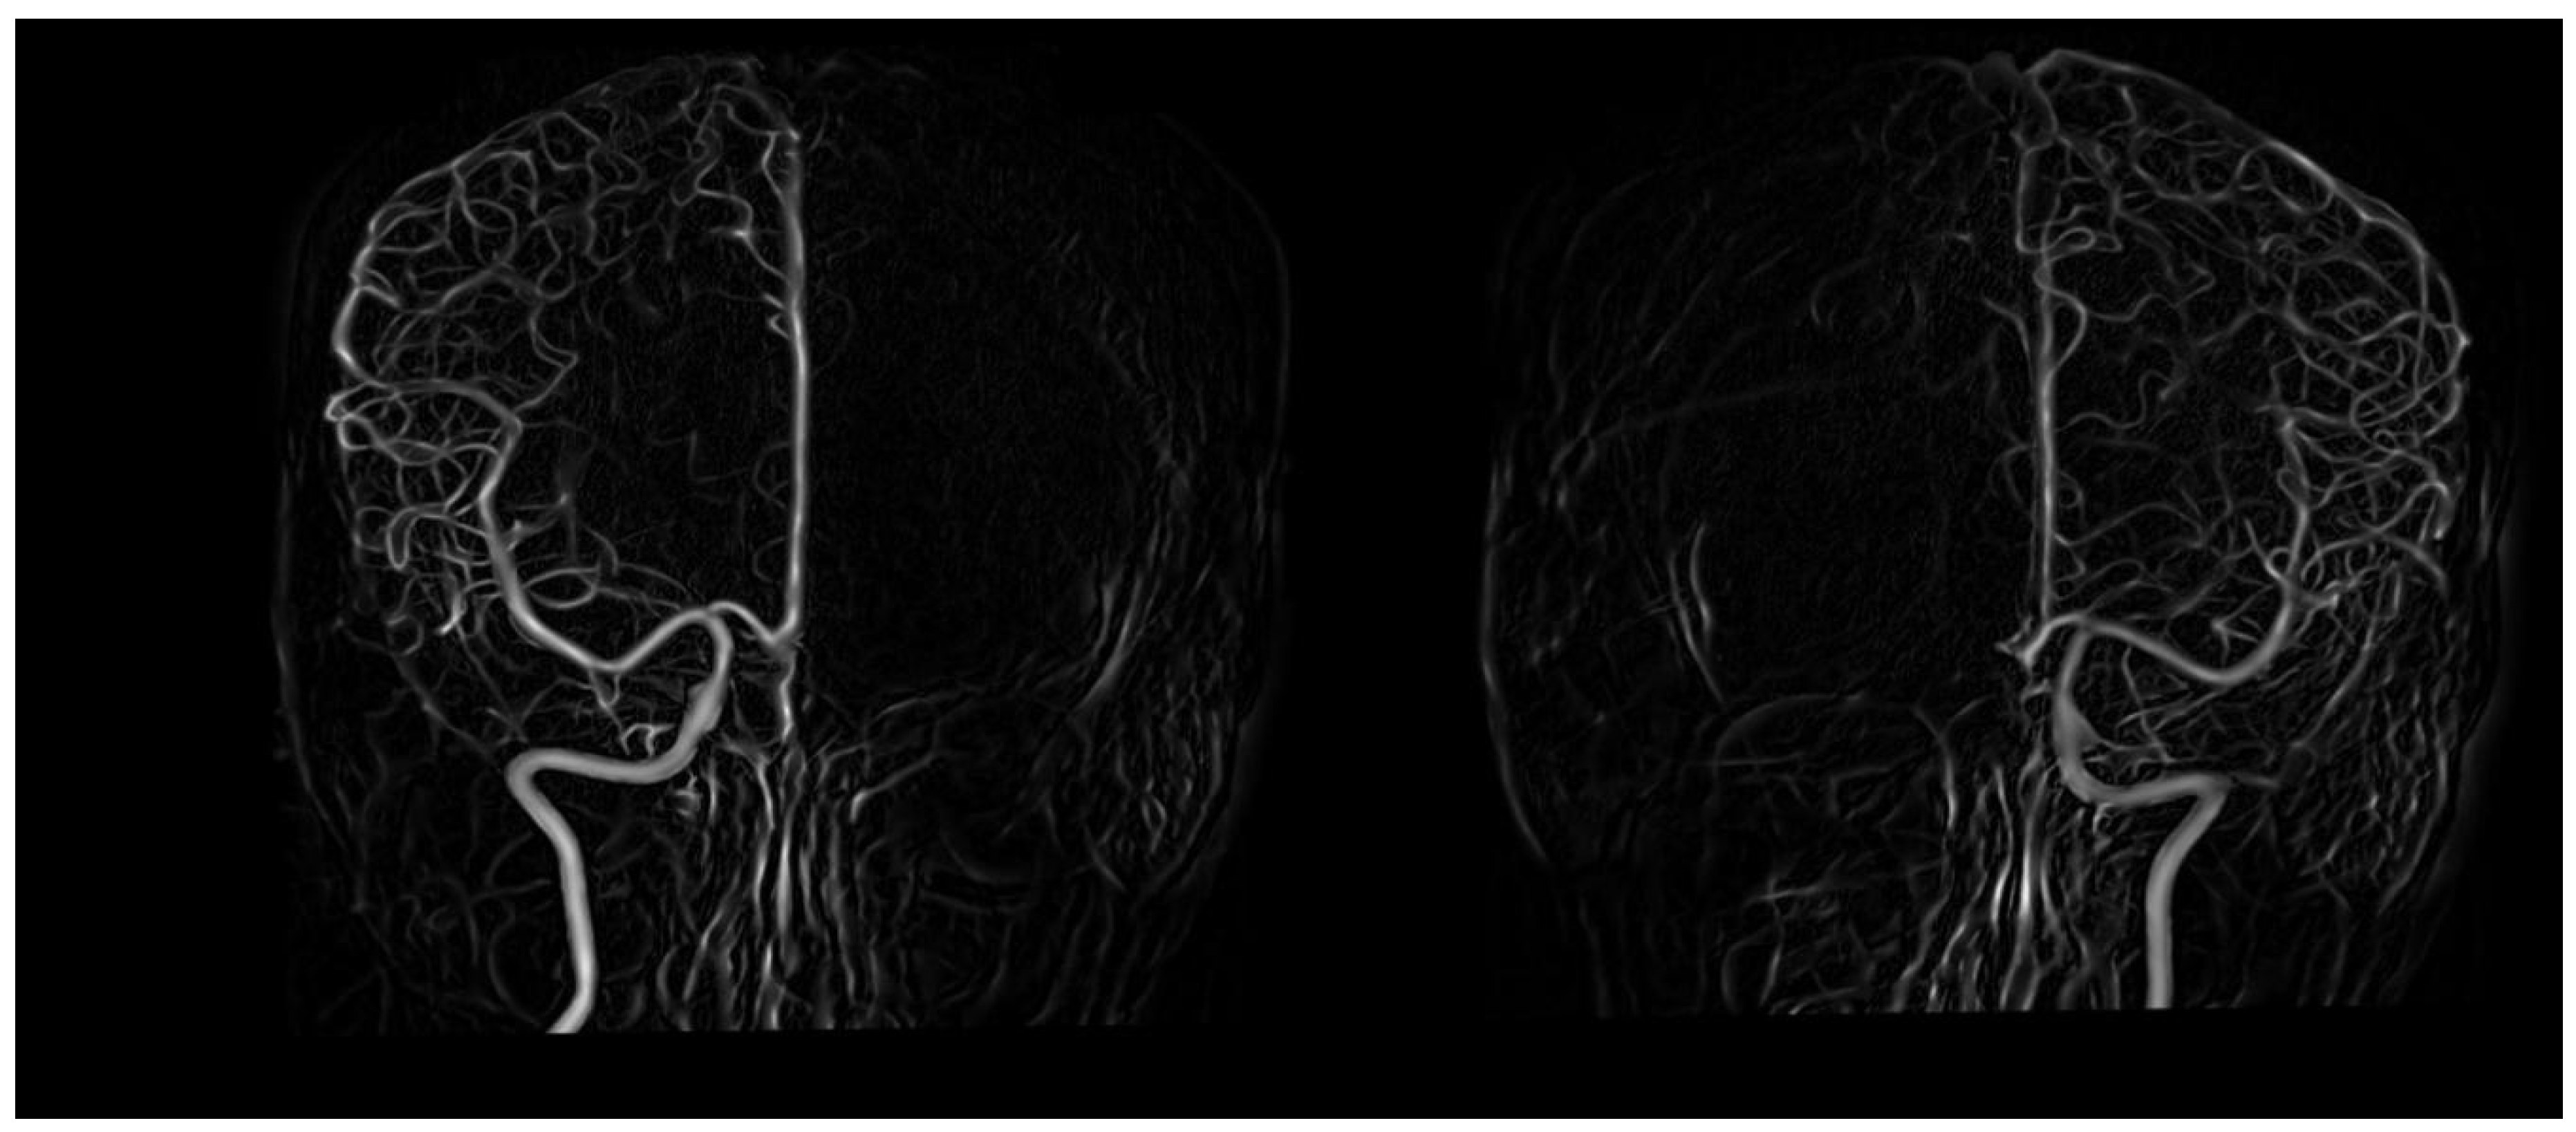

A new three-dimensional imaging technique has been developed that greatly improves the visibility of brain tumors in magnetic resonance imaging MRI scans. Brain scanning any of a number of diagnostic methods for detecting intracranial abnormalities. MEG is a new technology that measures the very faint magnetic fields that emanate from the head as a result of brain activity.

Bdcc Free Full Text Early Diagnosis Of Alzheimer Rsquo S Disease Using Cerebral Catheter Angiogram Neuroimaging A Novel Model Based On Deep Learning Approaches Html